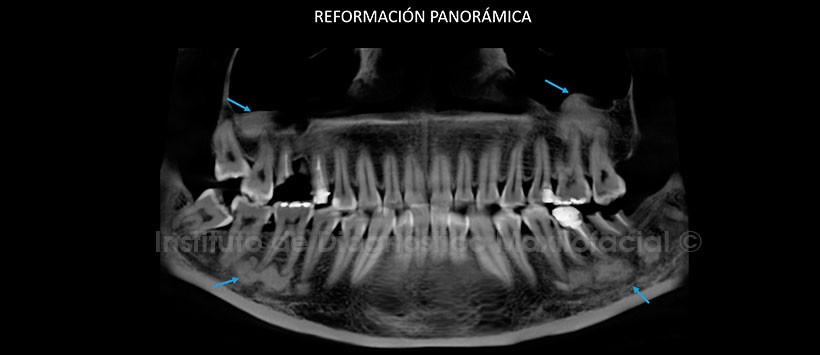

Al estudio mediante tomografía computarizada de haz cónico (CBCT), mediante reformación panorámica (Figura 2), cortes axiales (Figura 3) y coronales (Figura 4) se evidencia alteración del patrón de trabeculado óseo de manera focalizada a nivel apical de las piezas 1.8, 1.7, 2.6, 2.7, 3.5, 3.6, 3.7, 3.8, 4.5, 4.6 y 4.7. Presenta una densidad aumentada compatible con hueso y/o cemento.